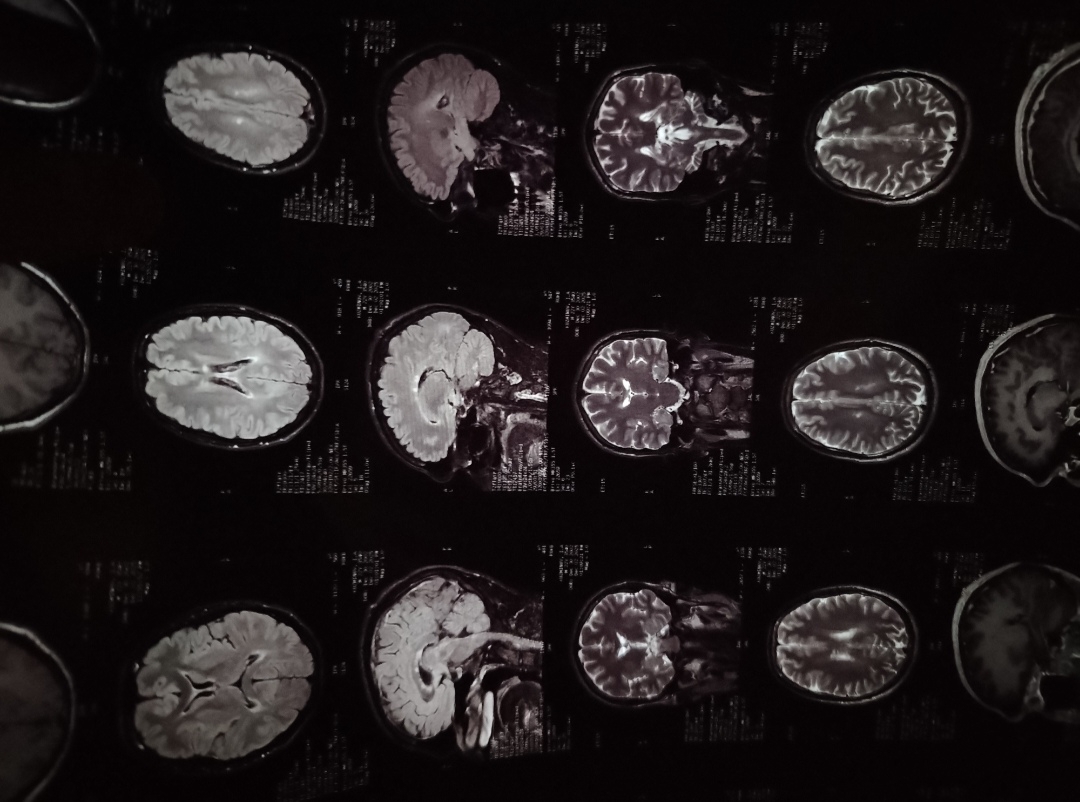

292404full.jpg

У анона в каком треде подобном диагностировали

Аноним 09/12/25 Втр 09:58:14 #121 №327477402

>>327477351

У него РС.